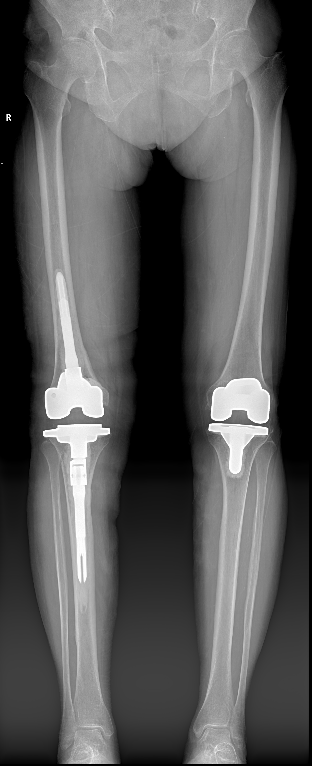

关节外科/运动医学科赵良军副院长、覃刚主任手术团队联合手术室、检验科及临床药学部等MDT团队为患者制定了周密的治疗方案,术前相关检查无明显手术禁忌症,在全麻下顺利完成右侧人工全膝关节表面置换术后感染清创、假体取出、新的假体按装等一期翻修手术。该手术在我院的成功开展,为髋膝关节置换术后感染患者提供了一套新的手术治疗方案。

图6 术后